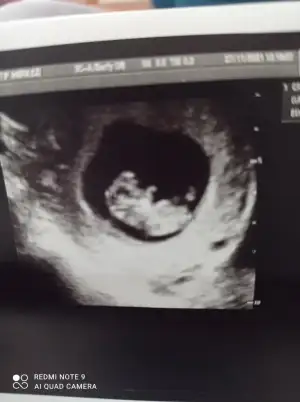

Seninki ne cano yorumlasin kuzum bende pek bilmiyorum. Ben ilk ocugunun cinsiyetini söylemişim. Senin ki de ortadaKarindan degil canim ikiside vajinal yukaridaki kizimin assagidaki yeni bebisimin ayni hafta ikiside kizim 7+4 yeni bebis 7+3 ayni günlerdeki ultrasyonlar